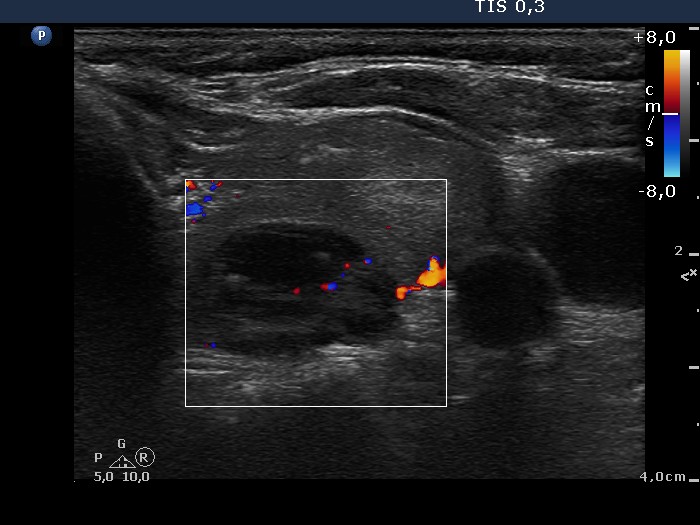

Ultrasonography. The thyroid was composed of multiple nodules with different echogenicities. There was a small hypoechogenic lesion above the right lobe.

Cytology was performed from the lesion above the thyroid and resulted in benign colloid goiter.